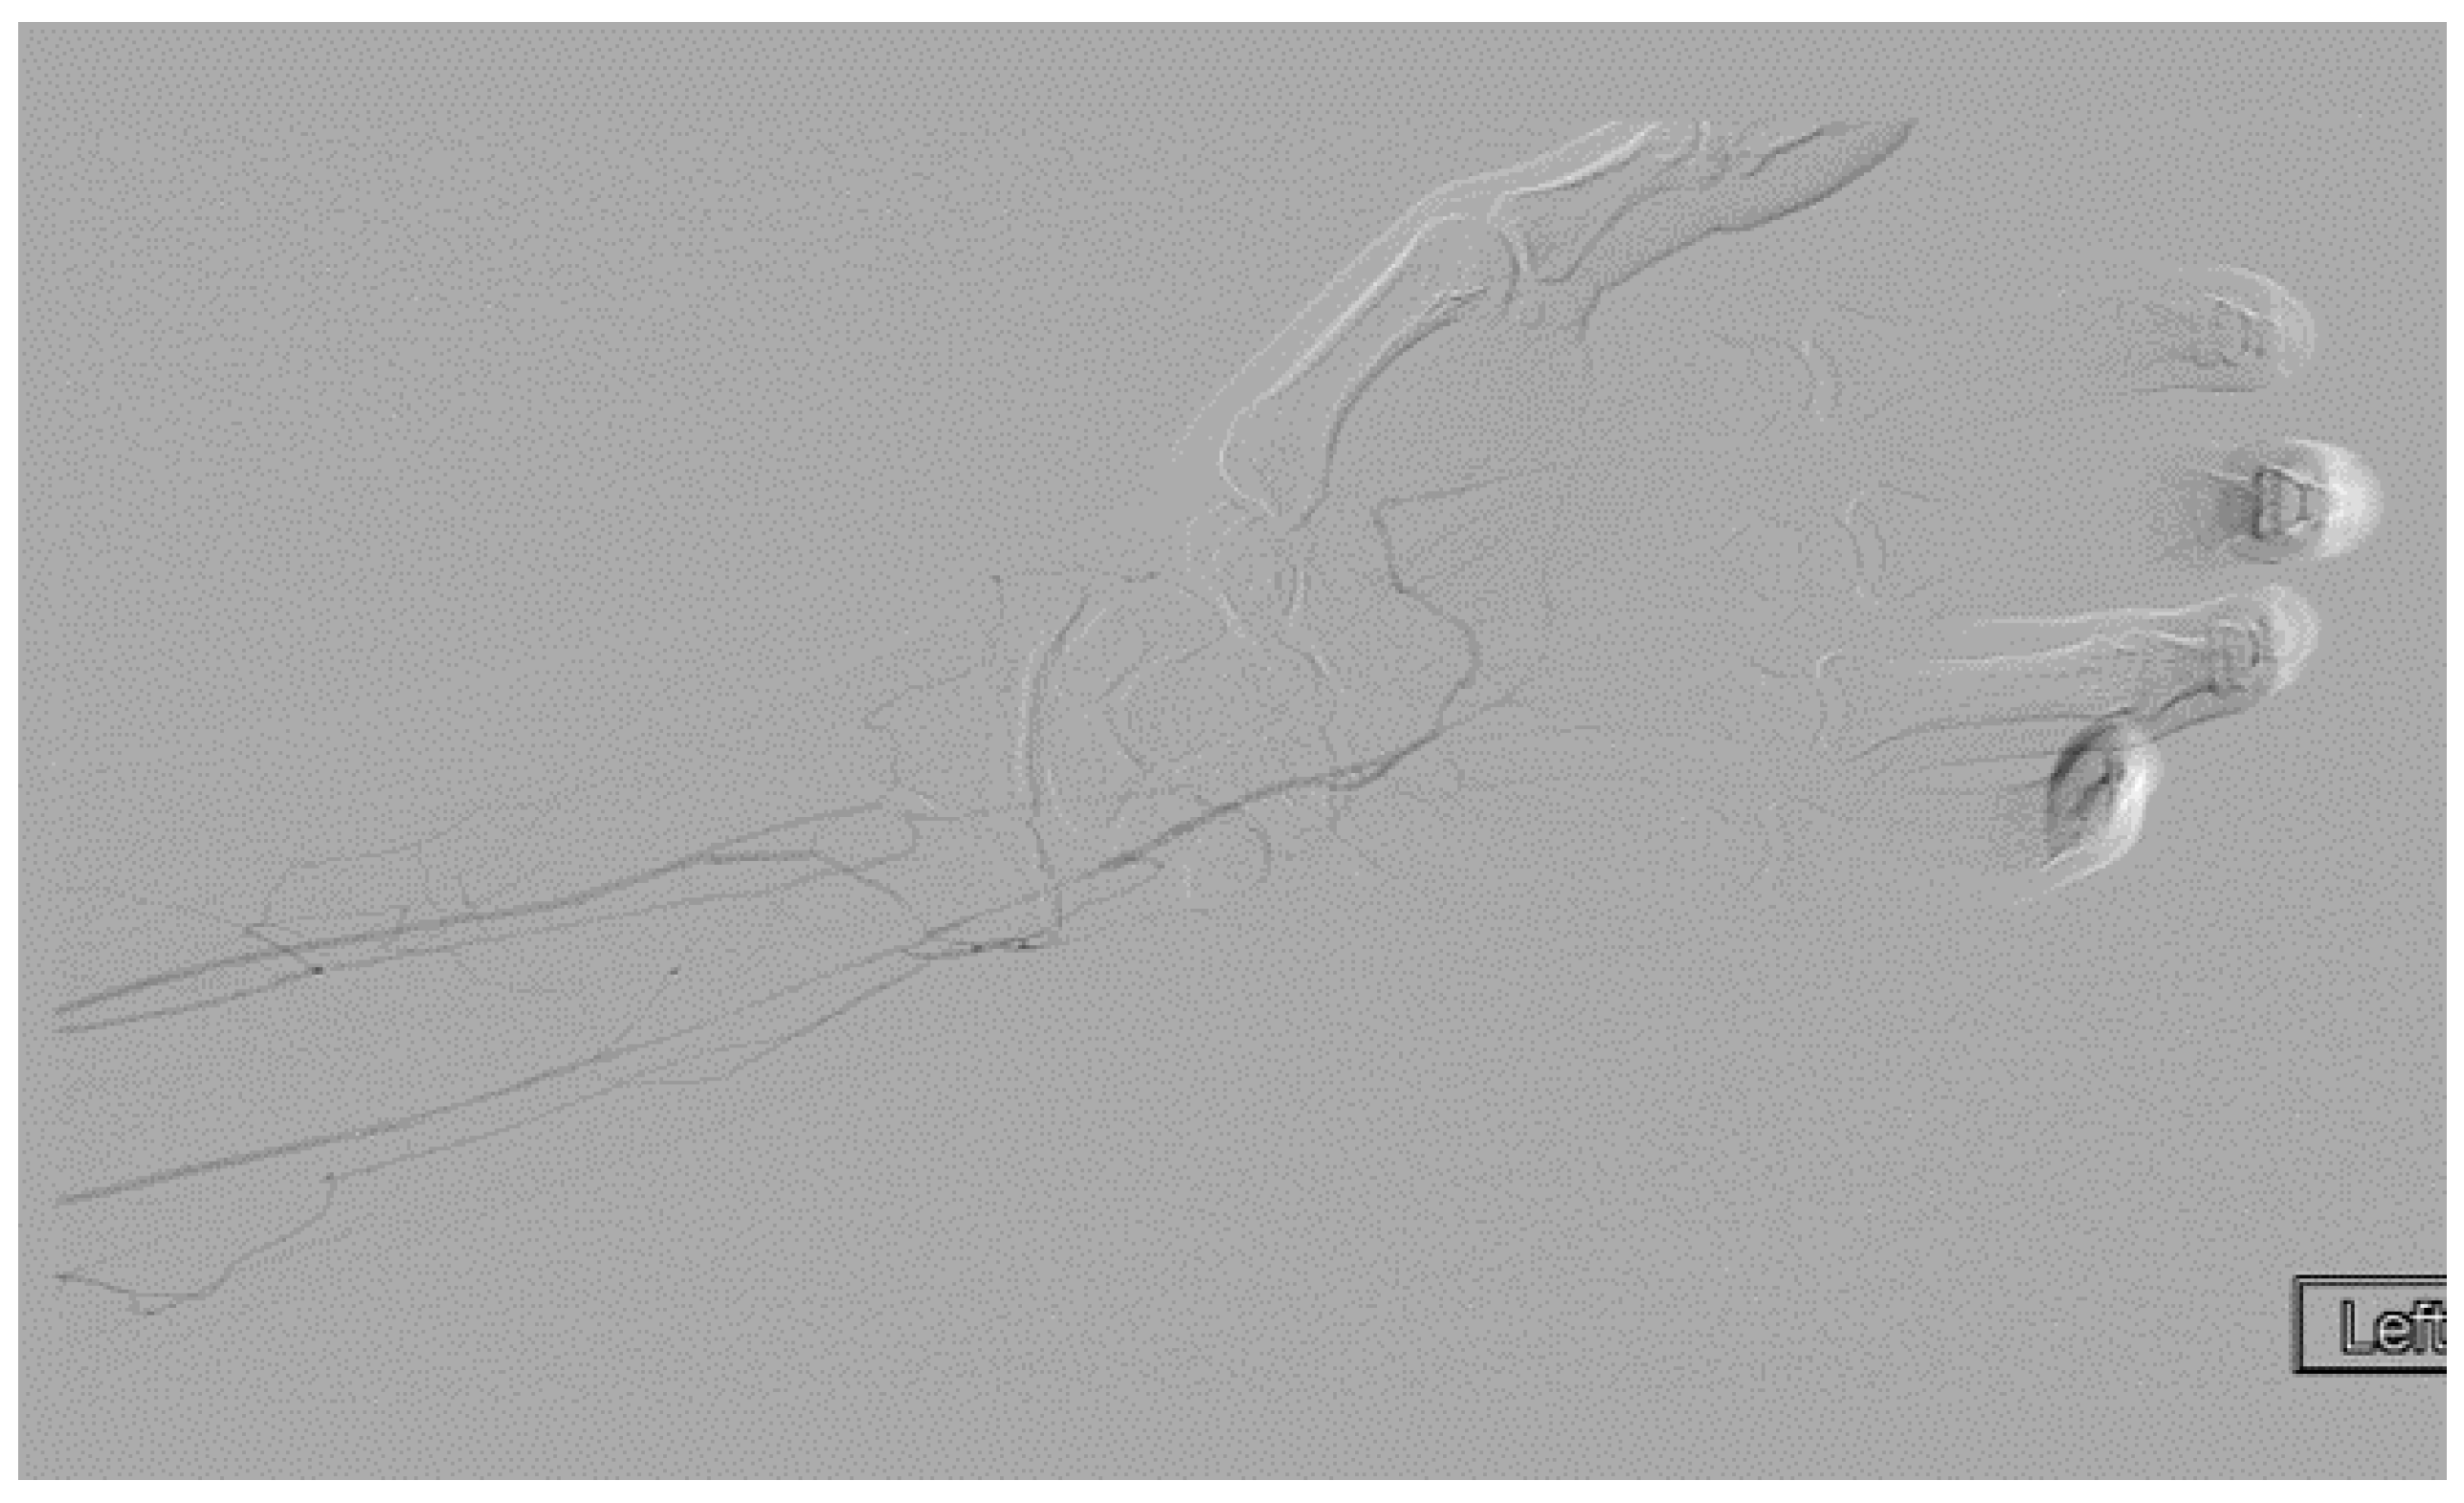

A heparin drip was then initiated, and she was taken to the catheterization lab for thrombolysis. This was carried out with Alteplase for 48 h as the patient had strong collaterals and was not in limb-threat (Figure 7, Figure 8, Figure 9, Figure 10 and Figure 11). However, her radial artery remained occluded. She was then taken to the operating room for thromboembolectomy of the left brachial and radial arteries (Figure 12). She was continued on anticoagulation post-operatively and was discharged.

Figure 11.

Distal brachial artery thrombosis in an ATOS patient.

Figure 12.

Excised thrombus from the brachial and radial arteries of an ATOS patient with a subclavian artery aneurysm.